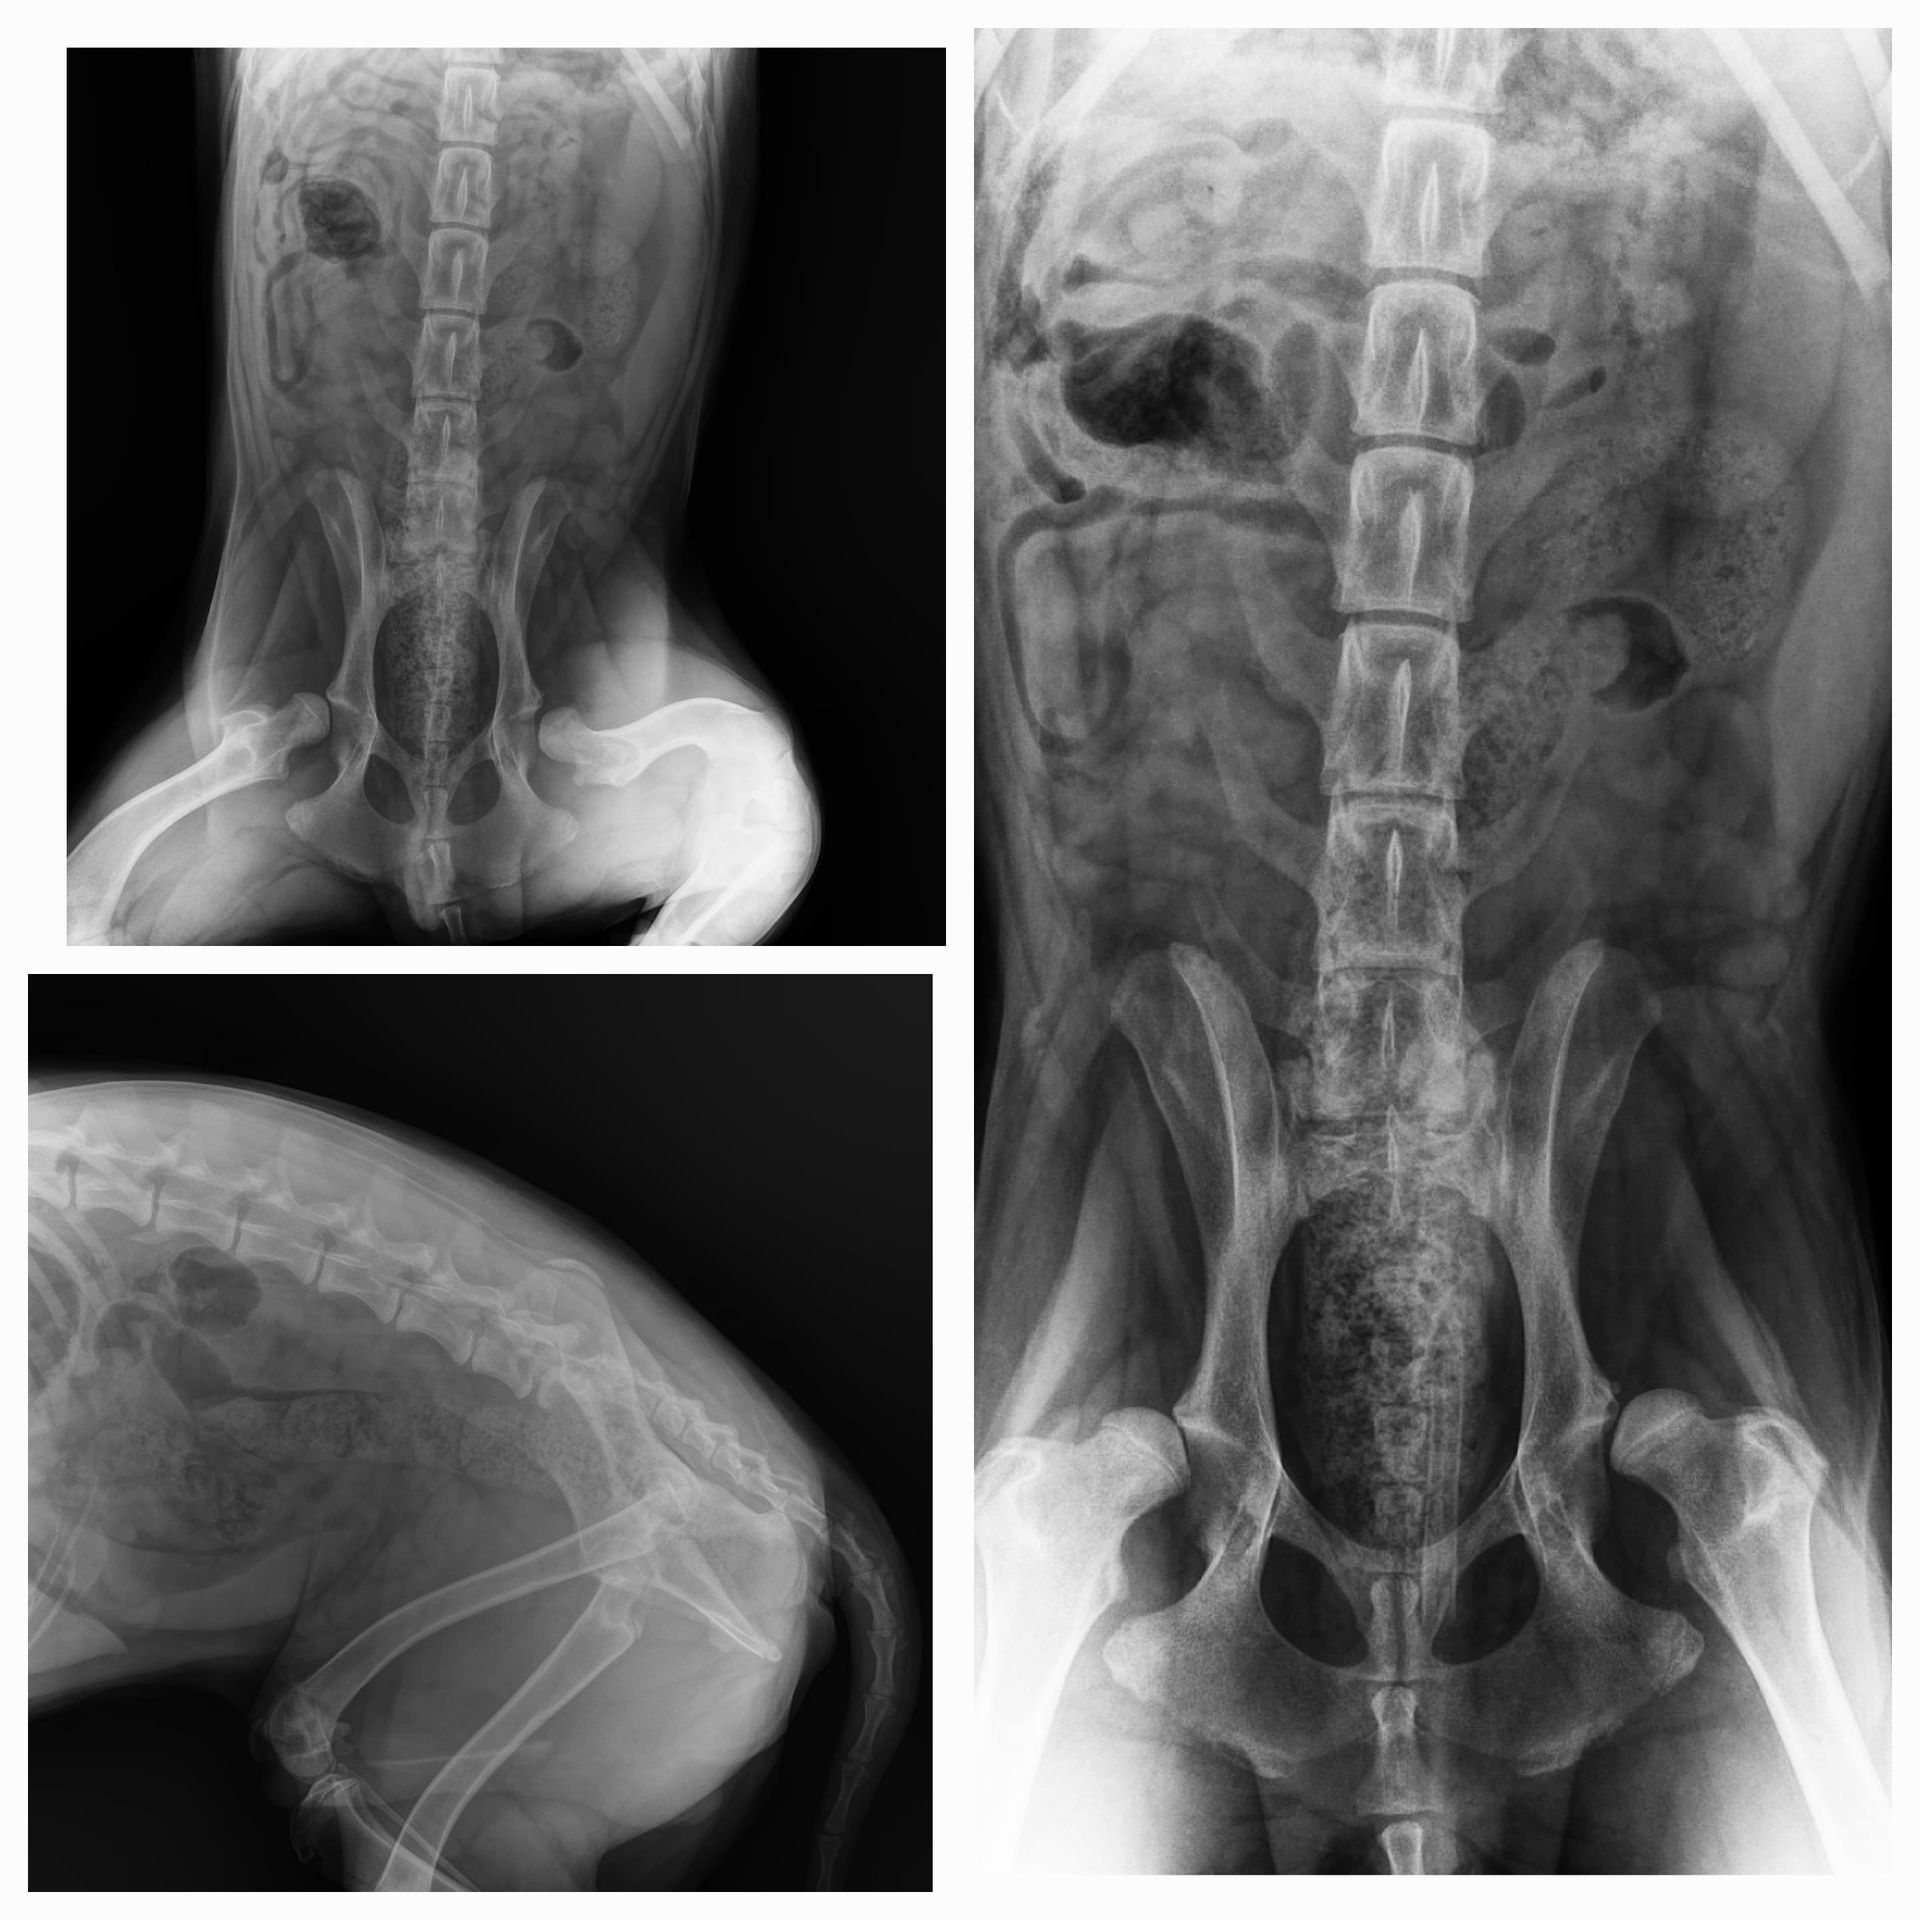

Die Ergebnisse der Röntgenaufnahme sind leider nicht so gut! 😢

Gary hat eine Hüftgelenksdysplasie an beiden Hinterbeinen. Die Köpfe beider Oberschenkelknochen befinden sich außerhalb der korrekten Position, da die Hüftpfanne an anatomischer Tiefe verloren hat. Die Knochen sind ausgerenkt, und können nur auf chirurgischem Wege korrigiert werden, entweder durch Ersatz der Oberschenkelköpfe (dies wird von einem Kollegen in Athen durchgeführt) oder durch Entfernung der Köpfe und die Bildung eines Pseudogelenks (zwei Operationen im Abstand von 3 Monaten, Kosten 650€ pro Operation in unserer Klinik). Da Gary wirklich leidet, müssen diese Operationen sein, also 1300 € kommen hier mindestens auf uns zu.

Dafür suchen wir Paten für Gary